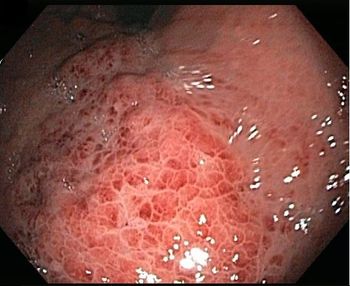

Cutaneous hyperpigmentation and papules coupled with active GI bleeding and a submucosal mass. What’s the diagnosis-and the chief clinical concern?